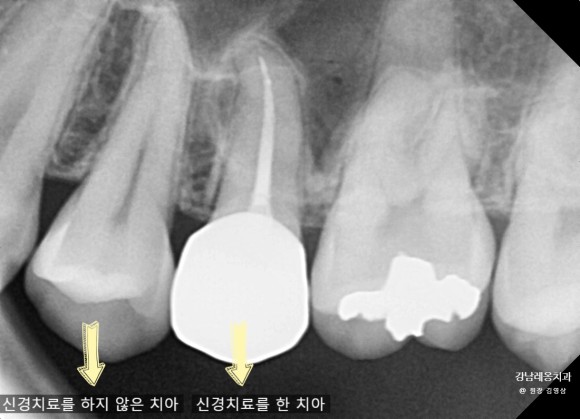

먼저 엑스레이를 통해 치아 내부 상태를 확인한 후 국소 마취를 합니다. 치료 과정에서 통증을 느끼지 않도록 도와줍니다.

신경치료 후 약해진 치아를 보호하기 위해 보철물(크라운)을 씌우는 경우가 많습니다.

- 신경치료 후 치아는 약해진다?

- 신경치료를 받은 치아는 치아 구조가 약해질 수 있지만, 크라운으로 보강하면 정상적인 기능을 유지할 수 있습니다.